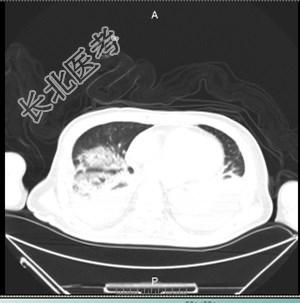

男性,70岁,农民。呼吸困难1小时。现病史:1小时前无诱因出现咳嗽,咳痰困难,呼吸急促,颜面部紫绀,意识模糊,急呼120来诊,急诊以“脑血管病,肺部感染”收入ICU。既往史:既往“糖尿病”11年,“脑出血”病史3年。长期卧床,自主咳痰能力差。查体:T:37.5℃,P:130次/分,R:25次/分,BP:94/50/mmHg。T:37.5℃P:130次/分,SpO

:24%BP:94/50mmHg营养不良,意识模糊,双侧瞳孔不等大。左:右=3:2mm,对光反射消失。听诊双肺呼吸音粗,可闻及大量湿性啰音及痰鸣音。四肢末端湿冷。辅助检查:FIO

/L,N%87.8%,血红蛋白:108g/LCRP:184.3mg/L血沉:40mm/hPCT:8.34ng/ml支气管镜下:支气管黏膜充血、水肿,可见少许食物残渣、大量白色粘痰。吸痰后各支气管腔均通畅。胸部CT:两肺多发渗出。痰培养:大肠埃希氏菌血培养:阴性支气管镜:镜下发现拉丝样白色粘痰